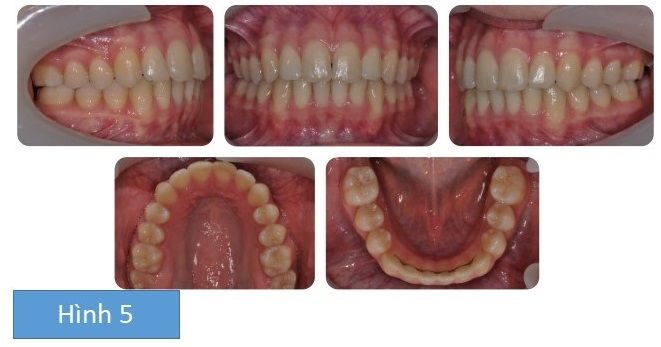

Kết quả cuối cùng được thể hiện ở Hình 5.